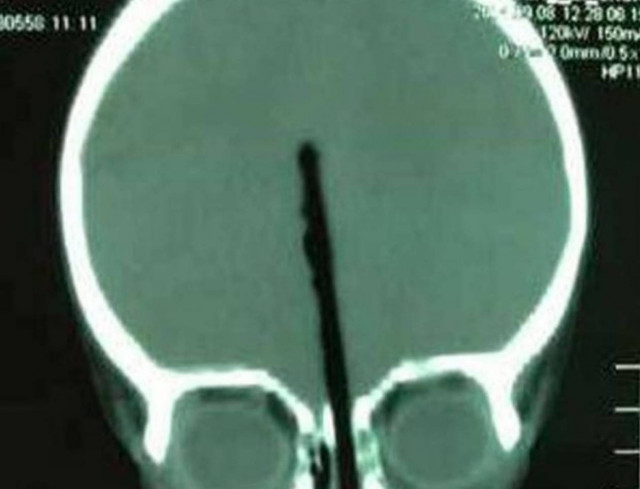

Φρίκη: Αγοράκι 2 ετών έβαλε ολόκληρο... τσόπστικ στη μύτη του

Ο μικρός Huang Zicheng από την Κίνα γλύτωσε από θαύμα, όταν πήρε ένα ξυλάκι τσοπτσίκ και το έβαλε στη μύτη του, τόσο βαθιά που παραλίγο να του προκαλέσει σοβαρή βλάβη στον εγκέφαλο

Ο πατέρας του μικρού από το Wuhan είπε στους γιατρούς ότι δεν ξέρει πως ακριβώς συνέβη το περιστατικό και ότι είδε το σοκαριστικό θέαμα όταν άκουσε τον γιο του να κλαίει. Aμέσως έτρεξε στο νοσοκομείο, καθώς παρόμοια περιστατικά έχουν αποδειχθή εξαιρετικά δύσκολα.

Σύμφωνα με την Metro, οι γιατροί χρειάστηκαν 4 ώρες μέχρι να αφαιρέσουν το ξυλάκι. Ευτυχώς ο δίχρονος νοσηλεύεται στο νοσοκομείο της περιοχής, πλέον εκτός κινδύνου.